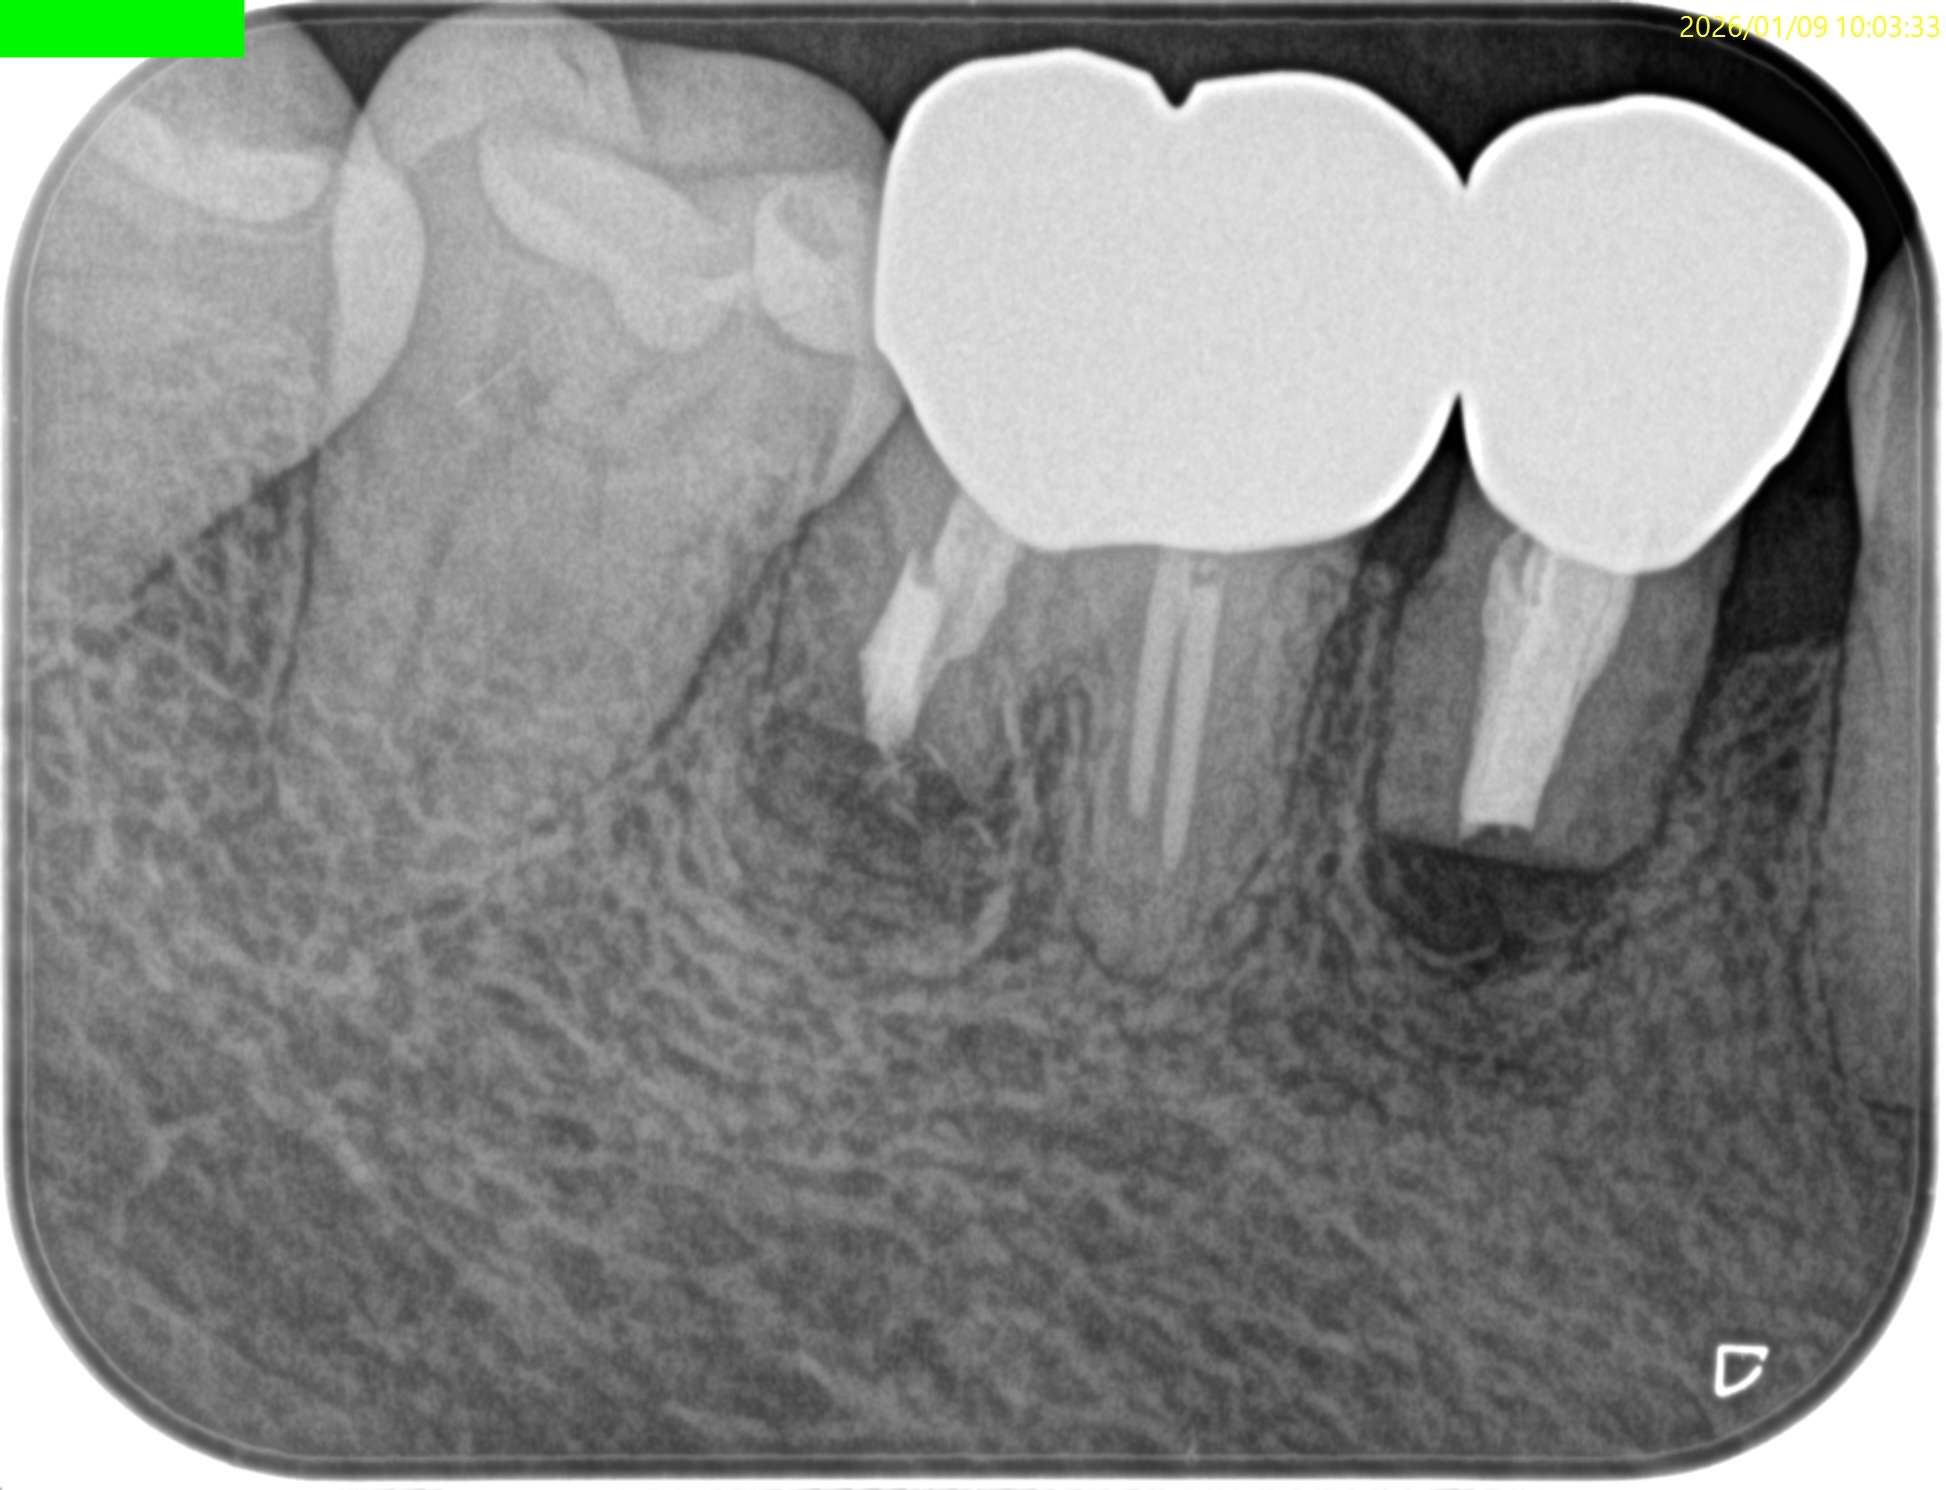

#29 Intentional Replantation 2M recall(2026.1.9)

PA, CBCTを撮影した。

歯槽骨は順調に回復している。